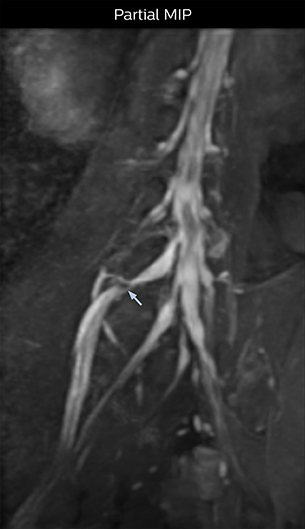

Because the obtained NerveVIEW images often exhibit a high signal in the intervertebral discs, we use partial MIP images to eliminate such intervertebral disc high signals. MIP image generation is based on the  center of the coronal stack, and RAO (right anterior oblique) and LAO (left anterior oblique) images rotated in the range of 45 degrees are used for diagnosis.

Distinguishing typical from atypical herniation informs the surgeon

“NerveVIEW is really useful for those cases where a nerve disorder is strongly suspected based on the clinical examination but our regular MRI images do not show any findings. These atypical herniations and spinal canal stenosis, occurring in 5% to 15% of the total lumbar herniation/stenosis cases are our main target when using NerveVIEW,” says Dr. Yabuki.

“Although symptoms of typical disc herniation and atypical hernia are very similar, the actual site of herniation is different. It is therefore important to characterize the nerve’s condition both inside and outside of the intervertebral foramina.